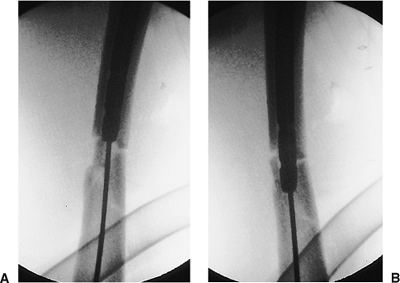

Figure 21.31. A,B.

Proper ball-tip guide-wire placement. A posteriorly placed wire can be seen as central on the AP view. This emphasizes the need to obtain both views to confirm containment of the wire in the medullary canal. |